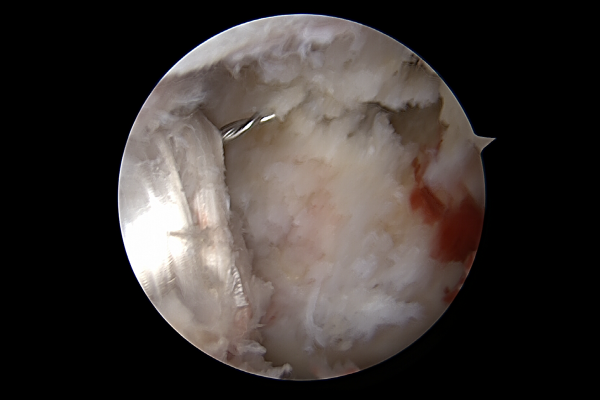

가이드 와이어에 실을 연결하여 재건한 인대를 올려줍니다.

최종적으로 잘 재건된 십자인대를 확인할 수 있습니다.